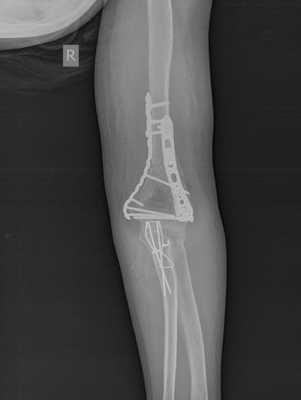

Пациентка Х, 54 лет, получила внутрисуставной Y-образный перелом мыщелков плеча. Смещение костных отломков настолько значительно, что диафиз плечевой кости близок к тому чтобы перфорировать кожу.

В случае настолько грубого смещения при первичном осмотре целесообразно выполнить анестезию перелома и устранить смещение с фиксацией конечности в задней гипсовой лонгтеной повязке. После обследования и предоперационной подготовки пациентка взята в операционную. Выполнен остеосинтез при помощи пластин с угловой стабильностью Synthes.

Послеоперационные рентгенограммы показывают, что смещение отломков полностью устранено, нормальные взаимоотношения костей верхней конечности восстановлены.